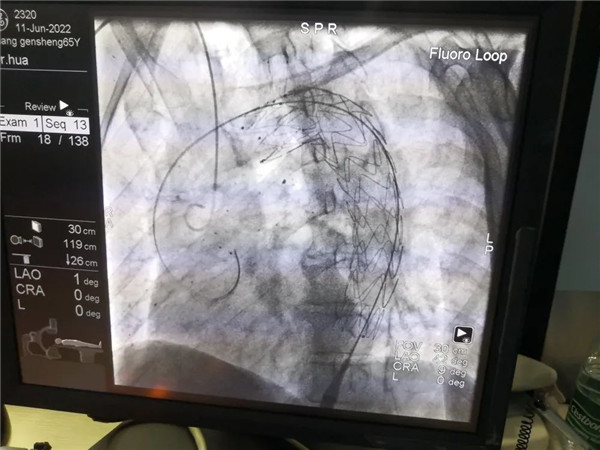

患者张某,突发胸痛3小时入院,入院血压210/115mmHg,胸痛持续不缓解。入院后完善主动脉CTA示:主动脉弓穿透性溃疡,主动脉壁间血肿。经心内科全体医师科室术前病例讨论后,拟行主动脉覆膜支架腔内隔绝术,充分与患者及家属沟通并征得同意后,由华永平主任医师介入团队,于6月11日在局麻下为患者行主动脉覆膜支架腔内隔绝术,通过术前充分的准备,血压、心率控制达标,手术进行得非常顺利,术后造影支架在位良好,达到预期效果。术后患者胸闷胸痛明显改善,可行一般活动,心脑血管风险显著降低。